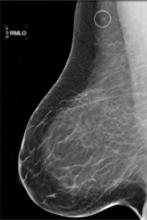

AI is also helping simplify complex tasks and help reduce the reading time on involved exams. One example of this is in 3-D breast tomosythesis with hundreds of images, which is rapidly replacing 2-D mammography, which only produces 4 images. Another example is automated image reconstruction algorithms to significantly reduce manual work. AI also is now being integrated directly into several vendors' imaging systems to speed workflow and improve image quality.

In addition to women with dense breasts, there are also other women for whom mammographic screening is not really enough, which is why research needs to continue in this field. Dr. Wendie Berg, a leading breast cancer specialist, talks with ITN about new research and advancements in breast imaging technology.

Dr. Berg, MD, PhD, FACR, FSBI, is Professor of Radiology at the University of Pittsburgh School of Medicine and Magee-Womens Hospital of UPMC, specializing in breast imaging. She is also the Chief Scientific Advisor to DenseBreast-info.org. A renowned expert, she writes and co-edits one of the leading textbooks on the topic, Diagnostic Imaging: Breast, currently in its third edition, and has co-authored over 120 peer-reviewed research publications.